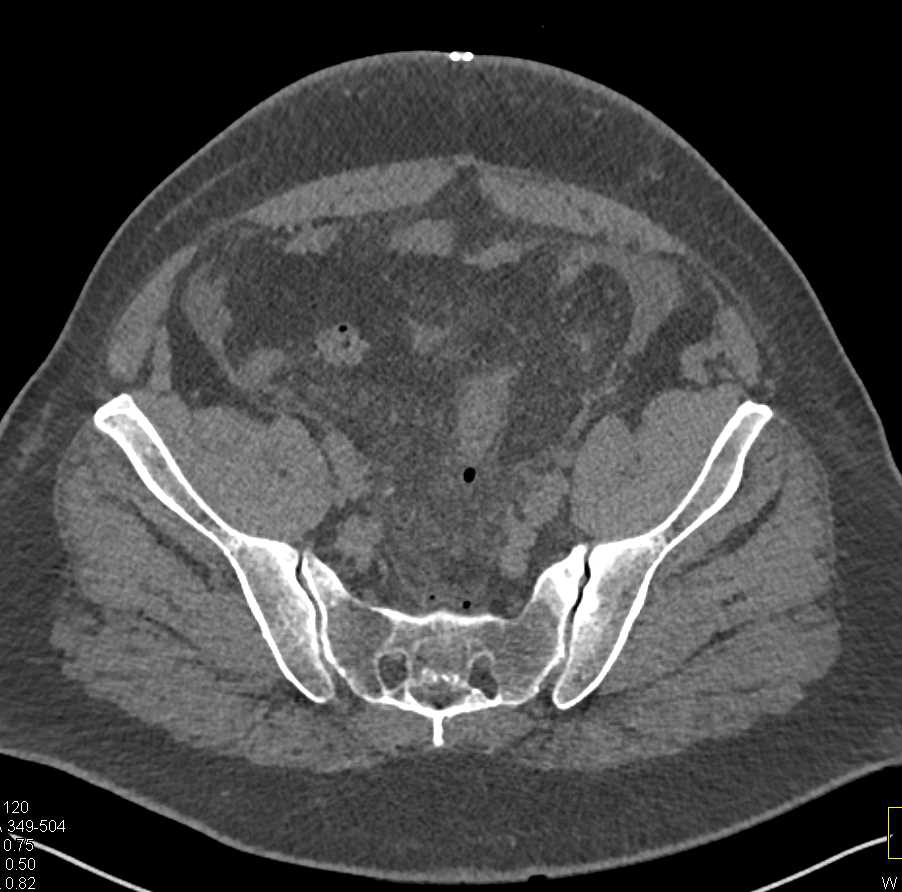

Appendicitis in a Pregnant Patient